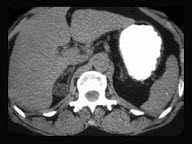

男,76岁,全身浅表淋巴结肿大,请结合下列图片作出诊断( )

A:肾上腺腺瘤

B:肾上腺癌

C:肾上腺嗜铬细胞瘤

D:肾上腺转移瘤

E:肾上腺淋巴瘤